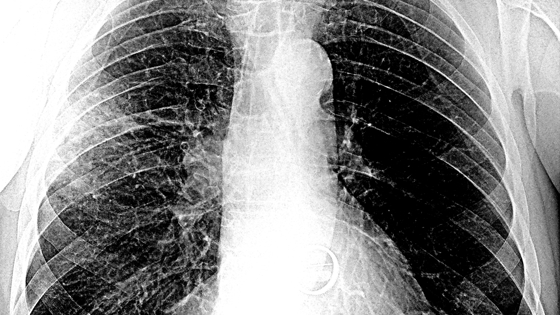

По словам эксперта, у «Омикрона» эффективные механизмы присоединения к рецепторам и проникновения в клетки человеческого организма. Поэтому он быстрее, чем другие варианты SARS-CoV-2, опускается в лёгкие, вызывая пневмонию. Если при других штаммах от момента заражения до развития пневмонии проходило 10-11 дней, сейчас этот период сократился до 3-5 дней.

При этом «Омикрон» немногим отличается от других штаммов. «Оно меняется и становится более эффективным, но мы пока всего не знаем. Тесты на нейтрализацию вируса занимают достаточно много времени, но биоинформатические исследования уже проведены во многих странах, в том числе и в России. И учёные не нашли ничего такого, что бы ставило свойства вируса с ног на голову. Что плохо в штамме «Омикрон», он точно так же, как и «Дельта», более тропен, то есть способен к взаимодействию с эпителием лёгких — нижних дыхательных путей. Поэтому «Омикрон» быстрее спускается в лёгкие, вызывая пневмонию. Это очень тревожно», — отметил Семёнов.